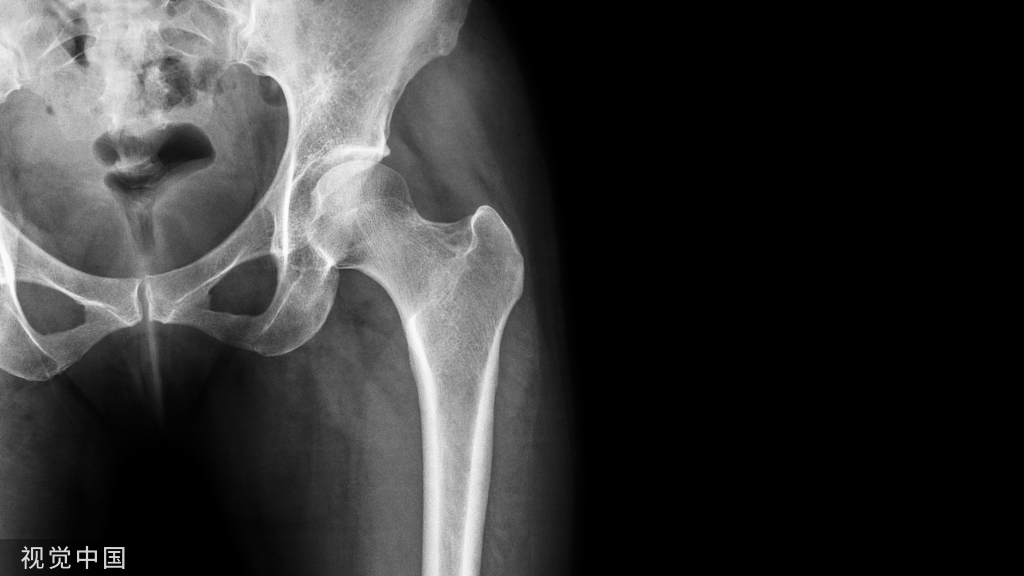

疲劳性骨折易发生部位及族群疲劳性骨折最容易发生的部位为下肢骨骼(胫骨、跗骨、跖骨、股骨、腓骨和种子骨),其次为腰椎、肋骨、肱骨、桡骨和尺骨。

若是位于较深处的构造,例如股骨,则疼痛可能会有扩散的情形;另外,虽然软组织肿胀的情形并不明显,特别是在活动之后有可能会发生。 通常运动时或运动后会感到疼痛,休息后,疼痛会消失或减缓;患者偶尔也会突然出现急性疼痛的情形。

疲劳性骨折的确诊疲劳性骨折会在患部有压痛点,或是已经愈合,会在患部摸到不平顺硬硬的组织,就是骨痂。

一般而言,会使用X-ray、Bone scan、CT、MRI等影像判别技术协助确诊,而Bone scan(骨扫描)的准确性是当中最高的。

因临床上无典型的外伤史,早期X线平片通常为阴性,容易漏诊或误诊。